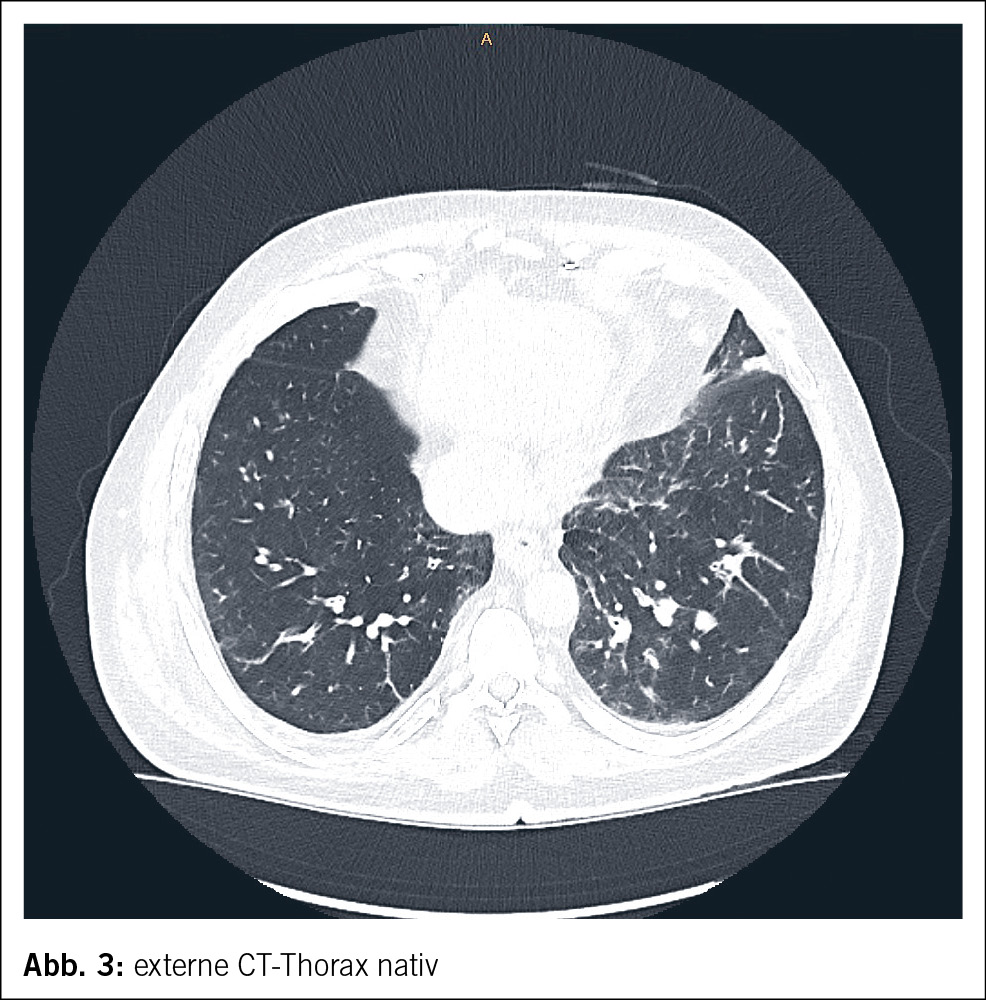

Ein 61-jähriger Mann wurde durch den Hausarzt bei Verdacht auf eine ambulant erworbene Pneumonie in ein wohnortnahes peripheres Spital zugewiesen. Neben purulentem Auswurf imponierten bei dortiger Aufnahme eine disseminierte leicht palpable Purpura (Abb. 1 und Abb. 2) mit enoraler Aussparung, ausgeprägte bilaterale Unterschenkelödeme sowie eine Bluteosinophilie von 3.1 G/l (0.0–0.7 G/l). In der CT-Thorax wurde eine basale Bronchiolitis mit weiteren bronchiolitischen Veränderungen im rechten Oberlappen ohne Konsolidationen oder Pleuraergüssen sowie Groundglass-Opazitäten in beiden Unterlappen nachgewiesen (Abb. 3). Eine antiinfektive Theapie mit Amoxicillin/Clavulansäure wurde initiiert, welche im Verlauf auf Ceftriaxon und Clarithromycin eskaliert wurde. Ausserdem veranlasste man eine Stanzbiopsie der Purpura im Bereich der streckseitigen Unterschenkel. Eine geplante diagnostische Bronchoskopie musste bei periinterventioneller hämodynamischer Instabilität und Sättigungsabfällen abgebrochen werden. Daraufhin erfolgte die Verlegung ins Universitätsspital Zürich zur weiteren pneumologischen Abklärung.

Unter der etablierten Therapie sahen wir eine rasche Normalisierung der Bluteosinophilie und der humoralen Entzündungsaktivität. Klinisch blasste die Purpura vollständig ab, weitere Fieberepisoden traten nicht auf. In der CT-graphischen Kontrolle ca. 2 Monate nach Therapieeinleitung waren die Groundglass-Opazitäten und bronchiolitischen Veränderungen vollständig regredient.